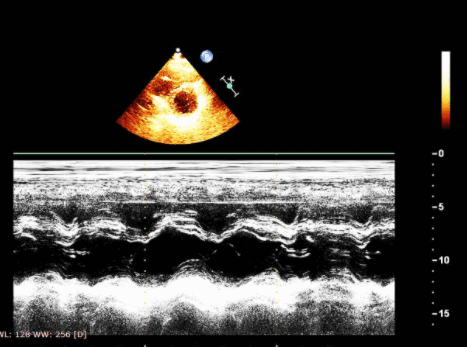

Несмотря на такие ограничения, для оценки размера и функции правого желудочка используются M-режим и 2-D эхокардиография. Лучшими ЭхоКГ доступами для ПЖ обычно являются:

Характерным электрокардиографическим поиском у пациентов с АДПЖ - это нахождение эпсилон-волны или локализованного удлинения комплекса QRS в правых грудных отведениях (в V1 -V3). Клинические признаки недостаточности правого желудочка и дисфункции левого желудочка, а также желудочковой тахикардии являются плохими прогностическими факторами. Трудно диагностировать АДПЖ без визуализации сердца, то есть без проведения эхокардиографии. Исследования правого желудочка в группе дисплазий показало, что эхокардиографические находки были у большинства пациентов с АДПЖ. Величина систолического и диастолического диаметров выводного тракта и притока были увеличены, причем было увеличение диастолического размера выводного тракта ПЖ (ВТПЖ), которые наиболее распространены.

Диаметр ВТПЖ был более 25 мм у всех пациентов. Если размер ВТПЖ больше, чем 30 мм по парастернальной длинной оси, то признак располагал значительной чувствительностью (90%) и специфичностью (88%) для диагностики АДПЖ. Функция ПЖ был ненормальный у 70% пациентов. Кроме того, региональные аномалии движения миокарда ПЖ на эхокардиографии были частыми, и наиболее значимыми в области верхушки и передней стенки. Морфологические нарушения ПЖ заключались в резко трабекулярной структуре внутренней выстилки, утолщении модераторного пучка, и присутствовии мешкообразных изменений в передней стенке ПЖ у 54%, 34% и 17% пациентов соответственно.